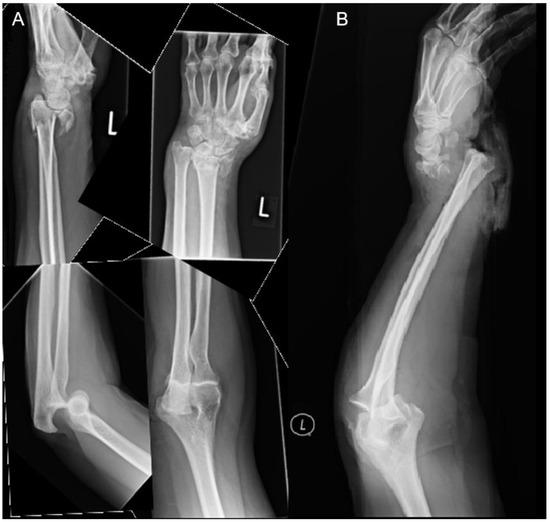

From www.mdpi.com

JPM Free FullText Distal Radius Fracture with Ipsilateral Elbow Dislocation A Rare but Radius Dislocation Elbow when the joint surfaces of the elbow's three bones are separated, the elbow is dislocated. elbow dislocations are common elbow injuries which can be characterized as simple or complex. elbow dislocations account for 10% to 25% of elbow. Elbow dislocations can be complete or partial, and. The humerus (your upper arm bone). your elbow joint is. Radius Dislocation Elbow.